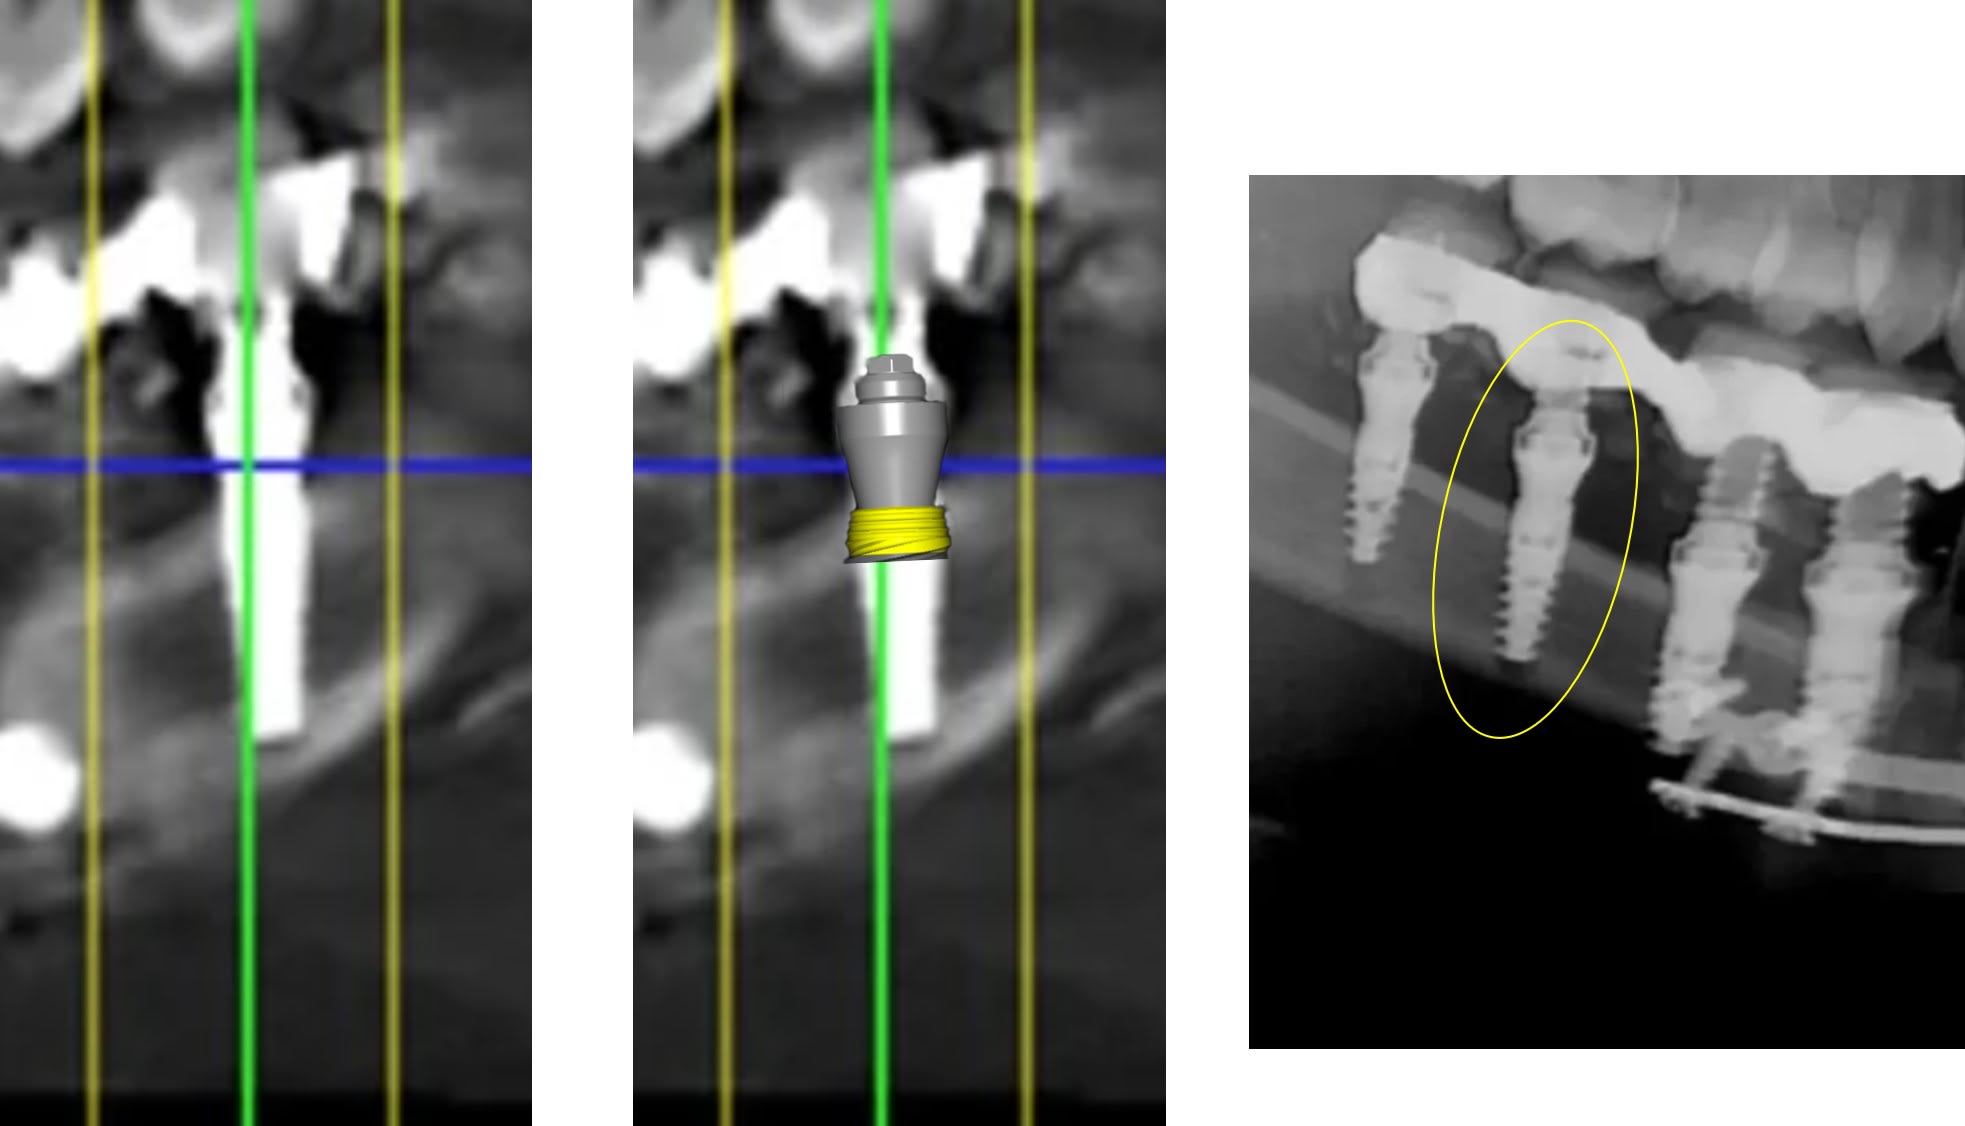

a parce qu il faut etre expert pour voir que les deux derniers implants sont clairement pas dans l os ??

1 se baser sur la pano pour en tirer des conclusions est une erreur de débutant

2 sur les coupes scanner une partie du col est infra osseuse et l'autre non

3 lorsque tu te permets le genre de commentaire que tu fais il faut être en mesure d'étayer un argumentaire

mais posit... y'a que toi qui pense que l'implant est aussi enfoui... ca saute aux yeux que tu fais tout pour grater 1mm d'enfouissement... pour qu'ils paraissent pas si mal posé que ca...

avec, par exemple, ton implant de 10mm qui est contenu dans 9mm... t'es le Gérard Majax des guides chir.

comme ici... si e carré fait 4,5 alors l’implant ne fait pas 10 mais moins de 9...

Tout comme l’autre implant pas 11,5 mais 10,3

heureusement que ta méthode est "précise" ;)

En traçant le col de l'implant comme tu le fais tu ne tiens pas compte que le pilier fait 4,5 mm de hauteur, normalement tu devrais arriver à le comprendre tout seul !

Pour le reste de la discussion que le col ne soit tout infra osseux oui mais pas "5 spires" et tout les implants sont en bi corticale. Lorsque tu dis à quelqu'un qu'il est de mauvaise foi vérifie en premier tes arguments. Pour le col dans un cas comme celui là ce n'est pas un problème.